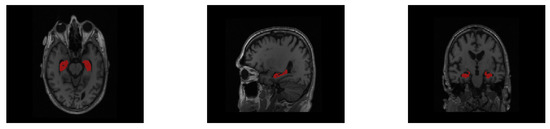

For convenience of display, the segmentation labels are mapped in the original images with the same resolution between the raw MRI image and its hippocampus segmentation label in the HarP and the MICCAI datasets. We set the corresponding hippocampus label pixel in the original MRI image to a specific value to represent the hippocampus, and other non-hippocampus pixels were kept unchanged to distinguish them from the hippocampus. The visualization segmentation results of the HarP and MICCAI datasets are displayed in Figure 6 and Figure 7, respectively. The area with a red pixel represents where the hippocampus is located, and other pixel values are non-hippocampus areas.

Figure 7. Three different dimensional slices of the multi-atlas labels on the MICCAI dataset.